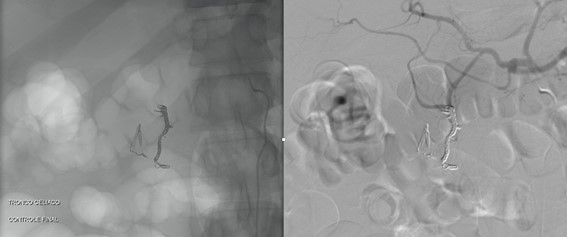

VIDEO: Com o micro cateter encravado foi realizada angiografia demonstrando passagem do meio de contraste para o interior do trato gastrointestinal, seguido de embolização Ruby Coils (Penumbra).

O caso em questão demonstra um achado endoscópico verdadeiro, demonstrando ainda natureza do sangramento intermitente.